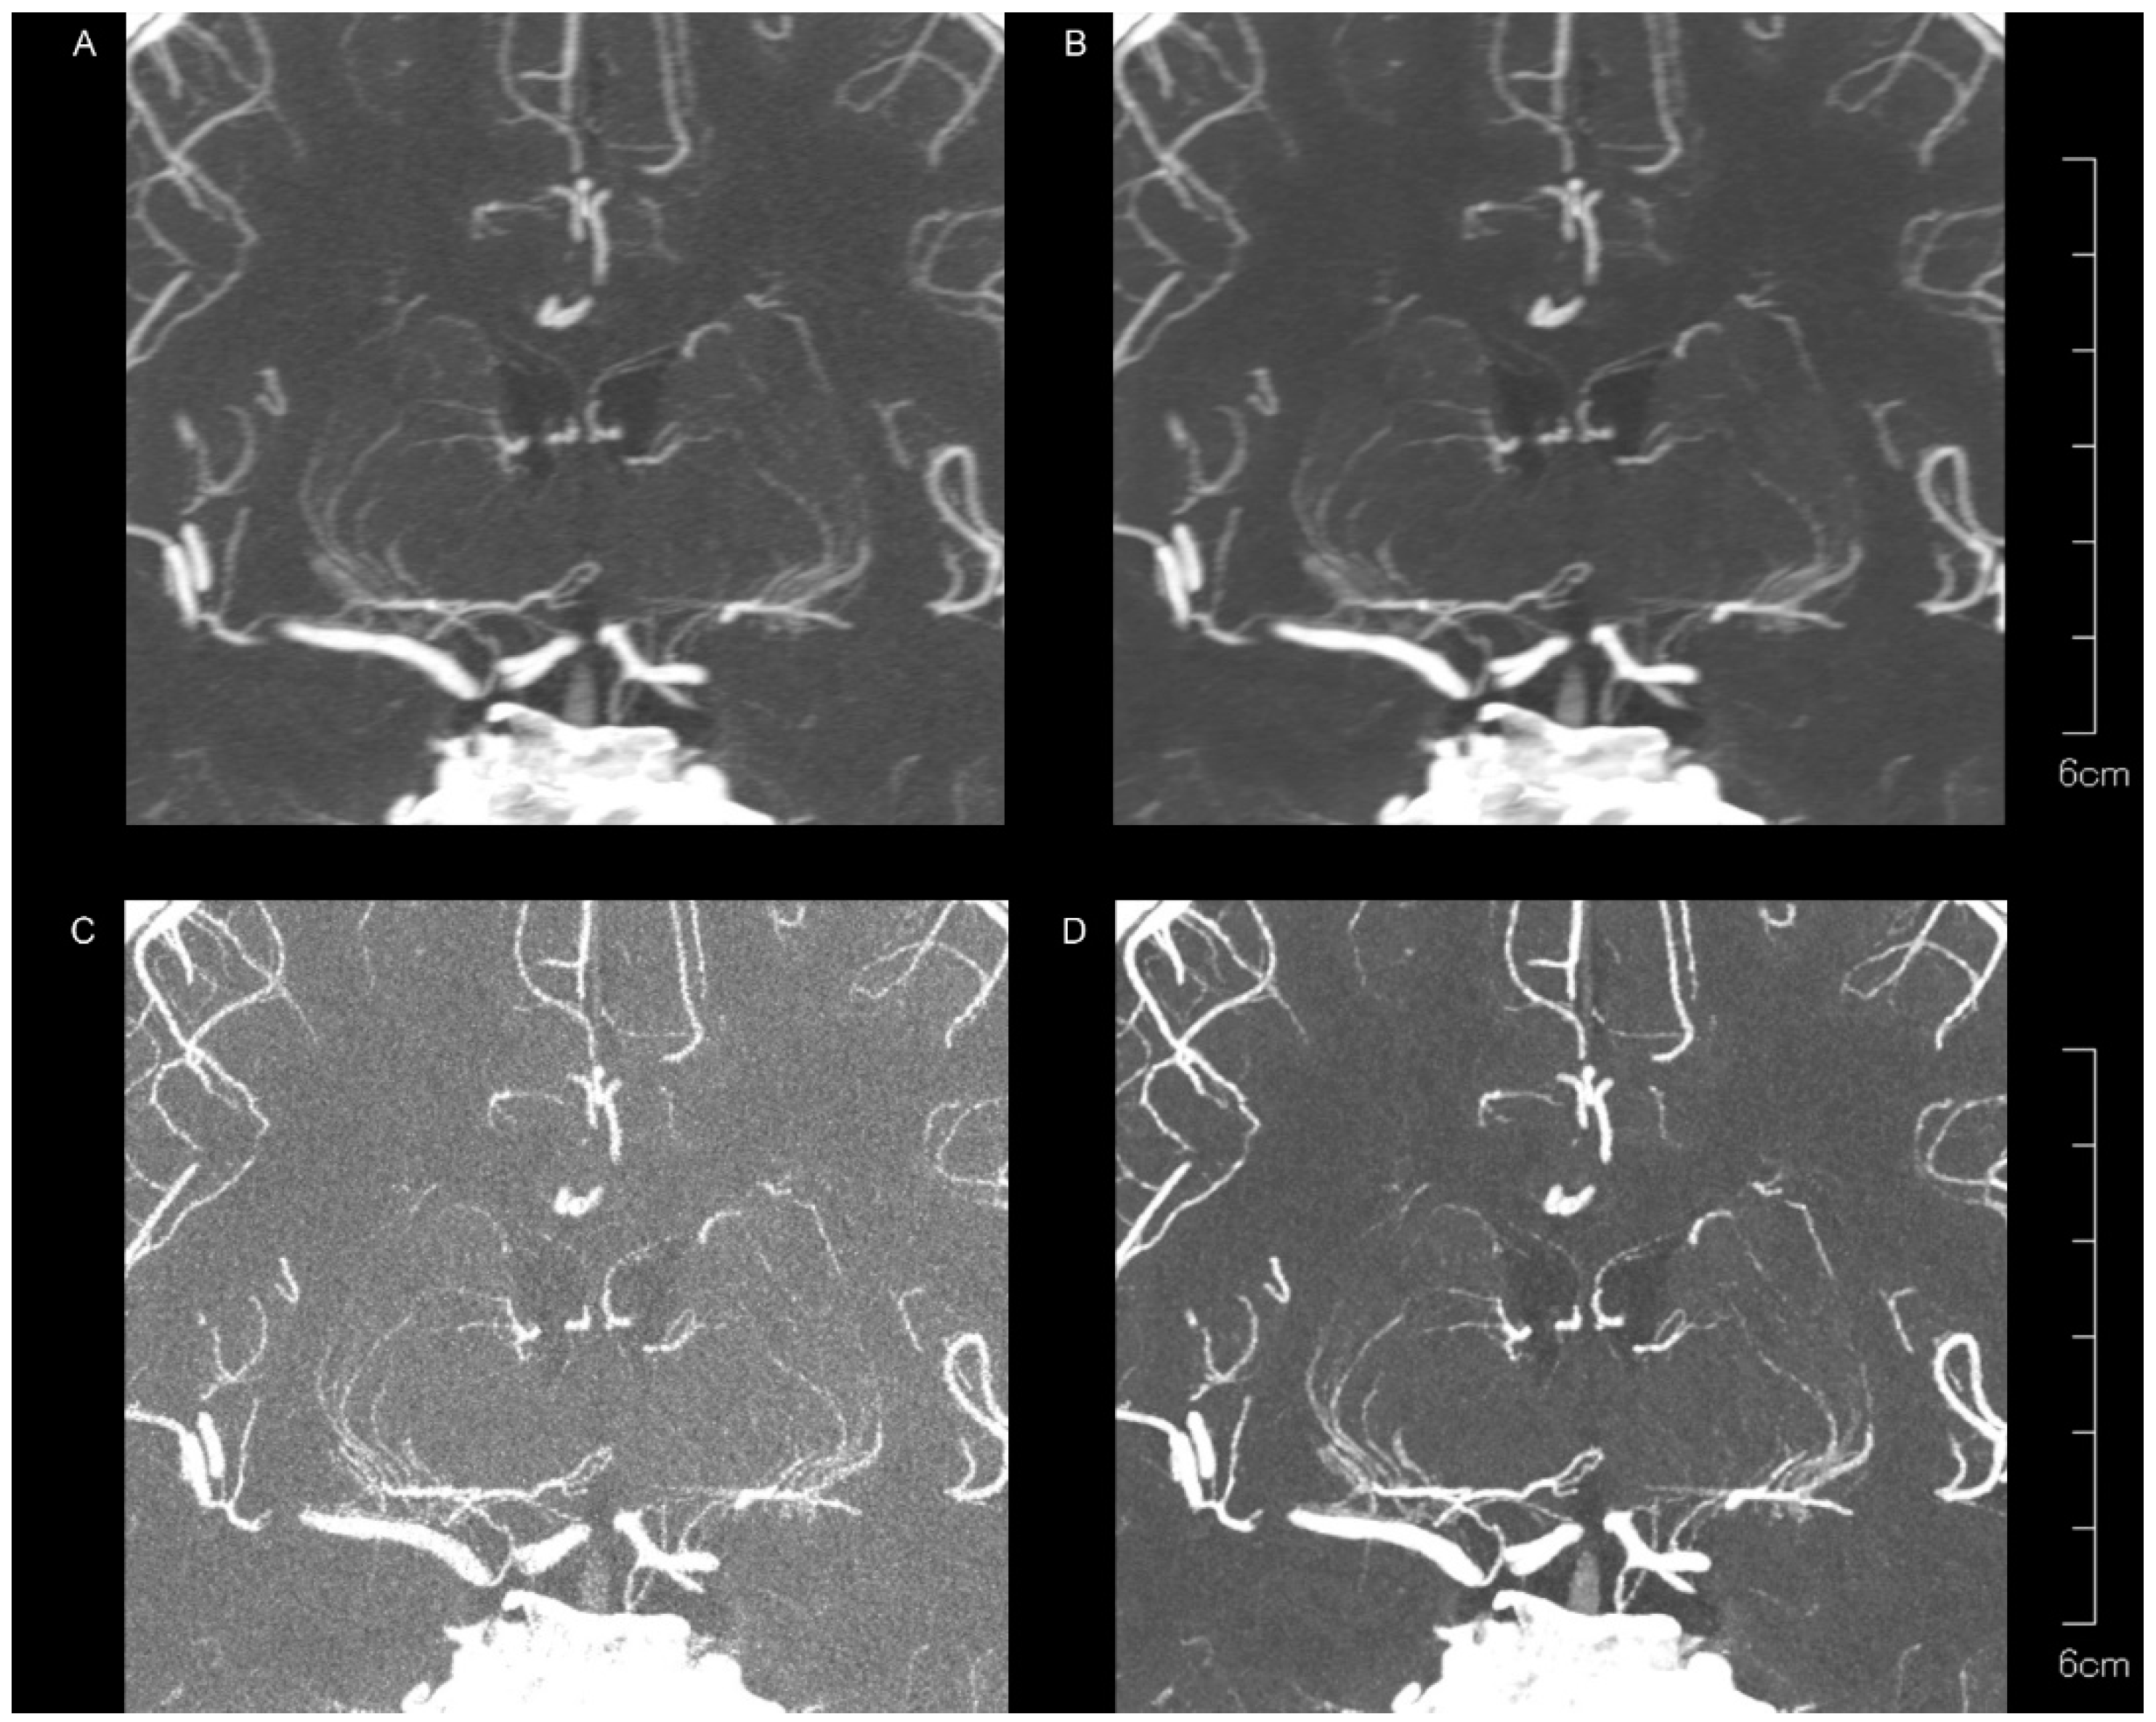

| LSA | Kernel Hv40 Without QIR | Kernel Hv40 with QIR | Kernel Hv72 Without QIR | Kernel Hv72 with QIR | p |

| Peripheral visibility | |||||

| Reader 1 | 3 (2–3) | 3 (2–3) | 3 (2–3) | 3 (3–3) | 0.293 |

| Reader 2 | 3 (3–3) | 3 (2–3) | 3 (2–3) | 3 (2–3) | 0.109 |

| Vessel sharpness | |||||

| Reader 1 | 1 (1–2) | 1 (1–2) | 1.5 (1–2) | 2 (1–2) | <0.00001 |

| Reader 2 | 1 (1–2) | 1 (1–2) | 2 (1–2) | 2 (2–2) | <0.00001 |

| Noise | |||||

| Reader 1 | 2 (1–2) | 2 (2–2) | 0 (0–0) | 1 (1–1) | <0.00001 |

| Reader 2 | 2 (1–2) | 2 (2–2) | 0 (0–0) | 1 (1–2) | <0.00001 |